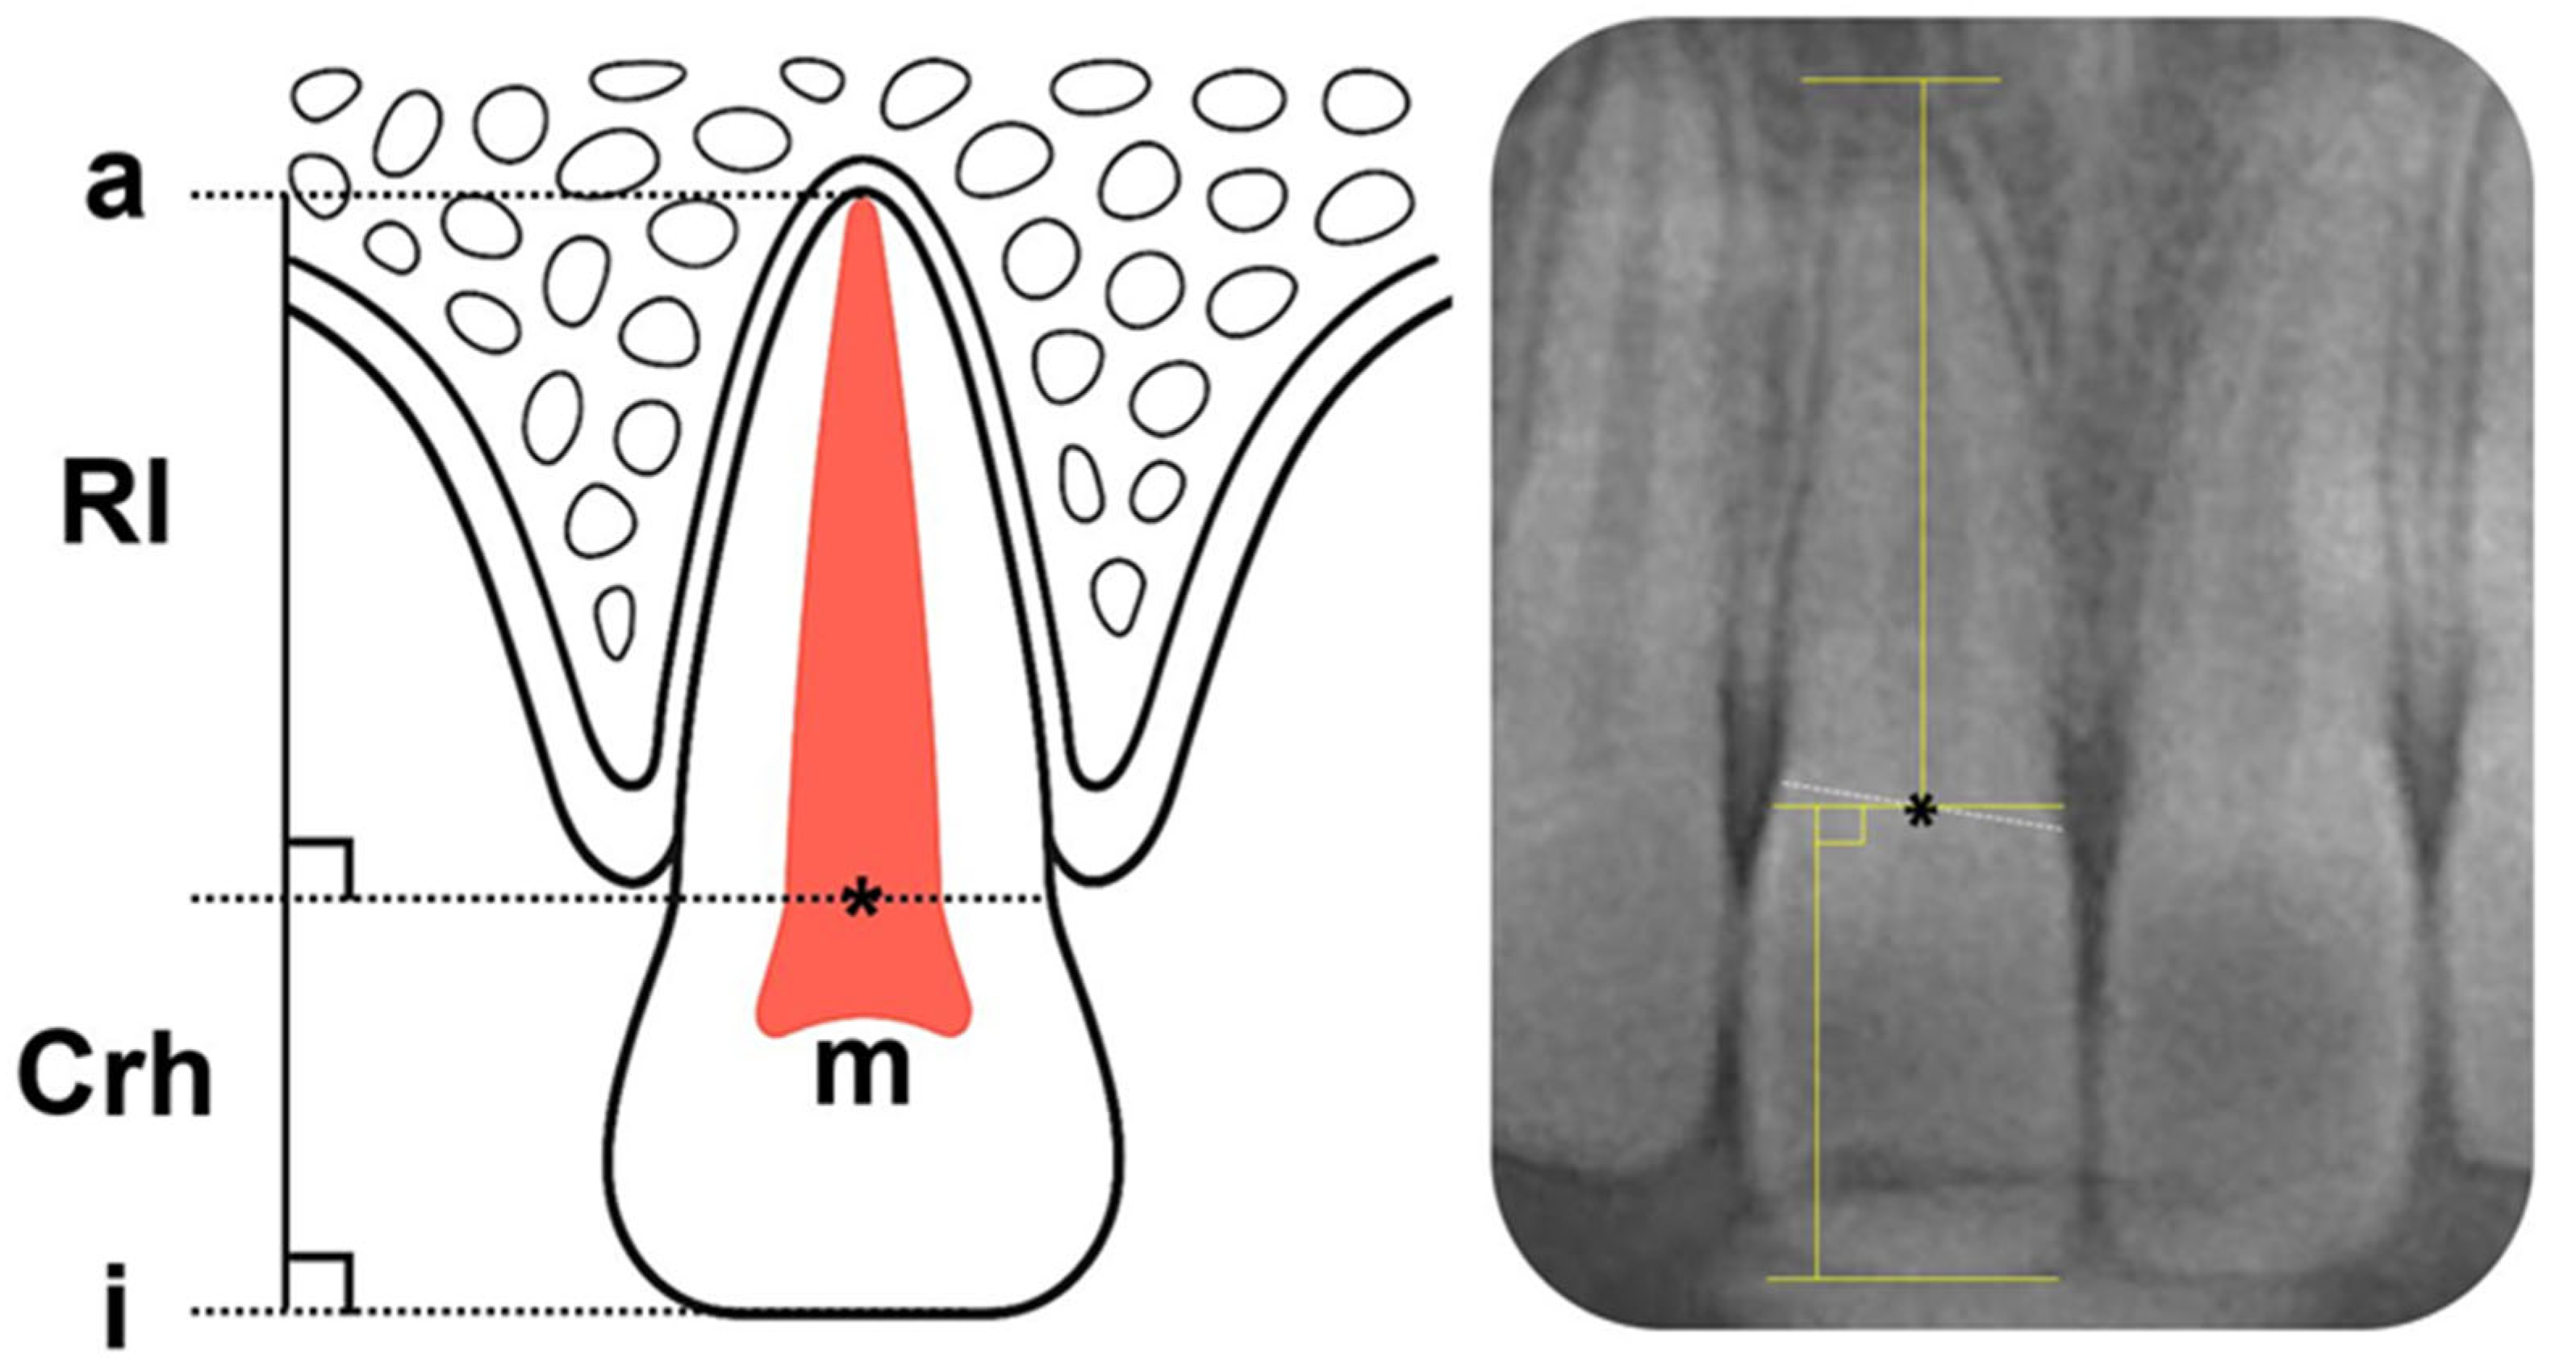

2.4. Study Methods